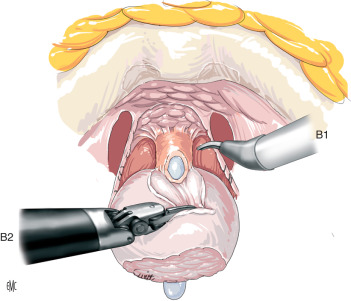

PROSTATECTOMIA ROBÓTICA

A PROSTATECTOMIA ROBÓTICA é uma técnica moderna e minimamente invasiva que utiliza uma plataforma robótica para melhorar a qualidade e precisão da cirurgia